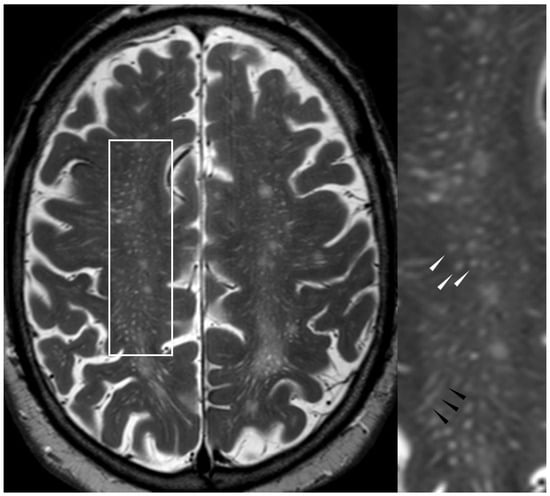

5.1.4. Cortical Superficial Siderosis

5.2.1. Enlarged Perivascular Spaces